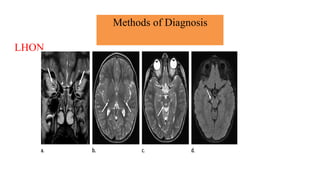

Brain magnetic resonance imaging

• Magnetic resonance imaging and spectroscopy are important tools in the diagnosis of

mitochondrial disorder.

• Brain atrophy is common in children with mitochondrial disease.

• Basal ganglia calcification are common in KSS and MELAS.

• Diffuse signal abnormalities of the white matter are characteristic of

KSS and myoneurogastrointestinal encephalopathy (MNGIE).

Methods of Diagnosis

Brain magnetic resonance imaging and spectroscopy

• The diagnosis of MELAS can be aided by the clinical association of stroke-like episodes with

radiological lesions that do not conform to the anatomical territories of blood vessels and

predominantly involve cortical gray matter.

• The initial or predominant lesions in MELAS are characteristically in the parietal- occipital

region.

• Leigh syndrome characteristically shows bilateral hyperintense signals on T2- weighted and

fluid-attenuated inversion recovery (FLAIR) MRIs in the putamen, globus pallidus and thalamus.

• MRS often detects lactate accumulation in the CSF and in specific areas of the

brain.

LHON